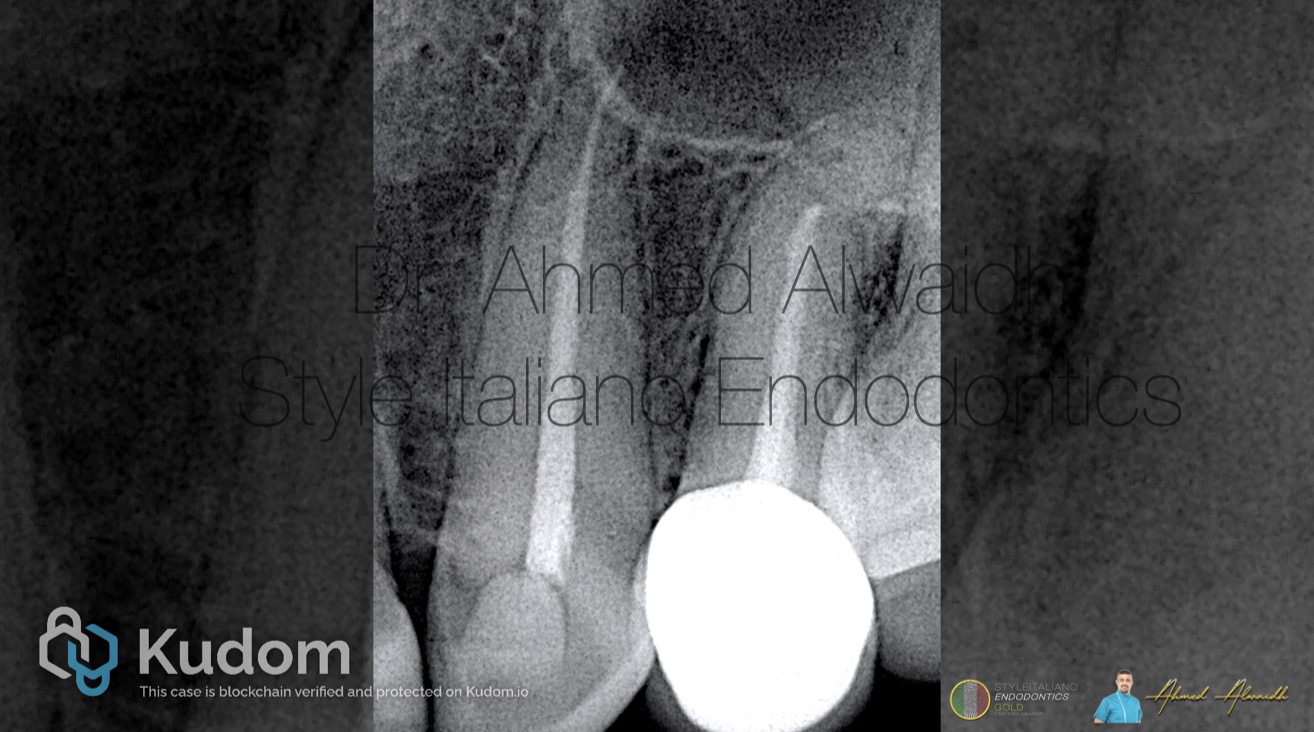

Fig. 1

A 40 years old female presented complaining of dull pain that increases during eating in her upper left canine. History of root canal treatment in UL3 around a year ago, and since then the symptoms started.

Clinically, UL3 was tender to percussion. IOPA revealed UL3 with existing root canal treatment, and peri apical changes.